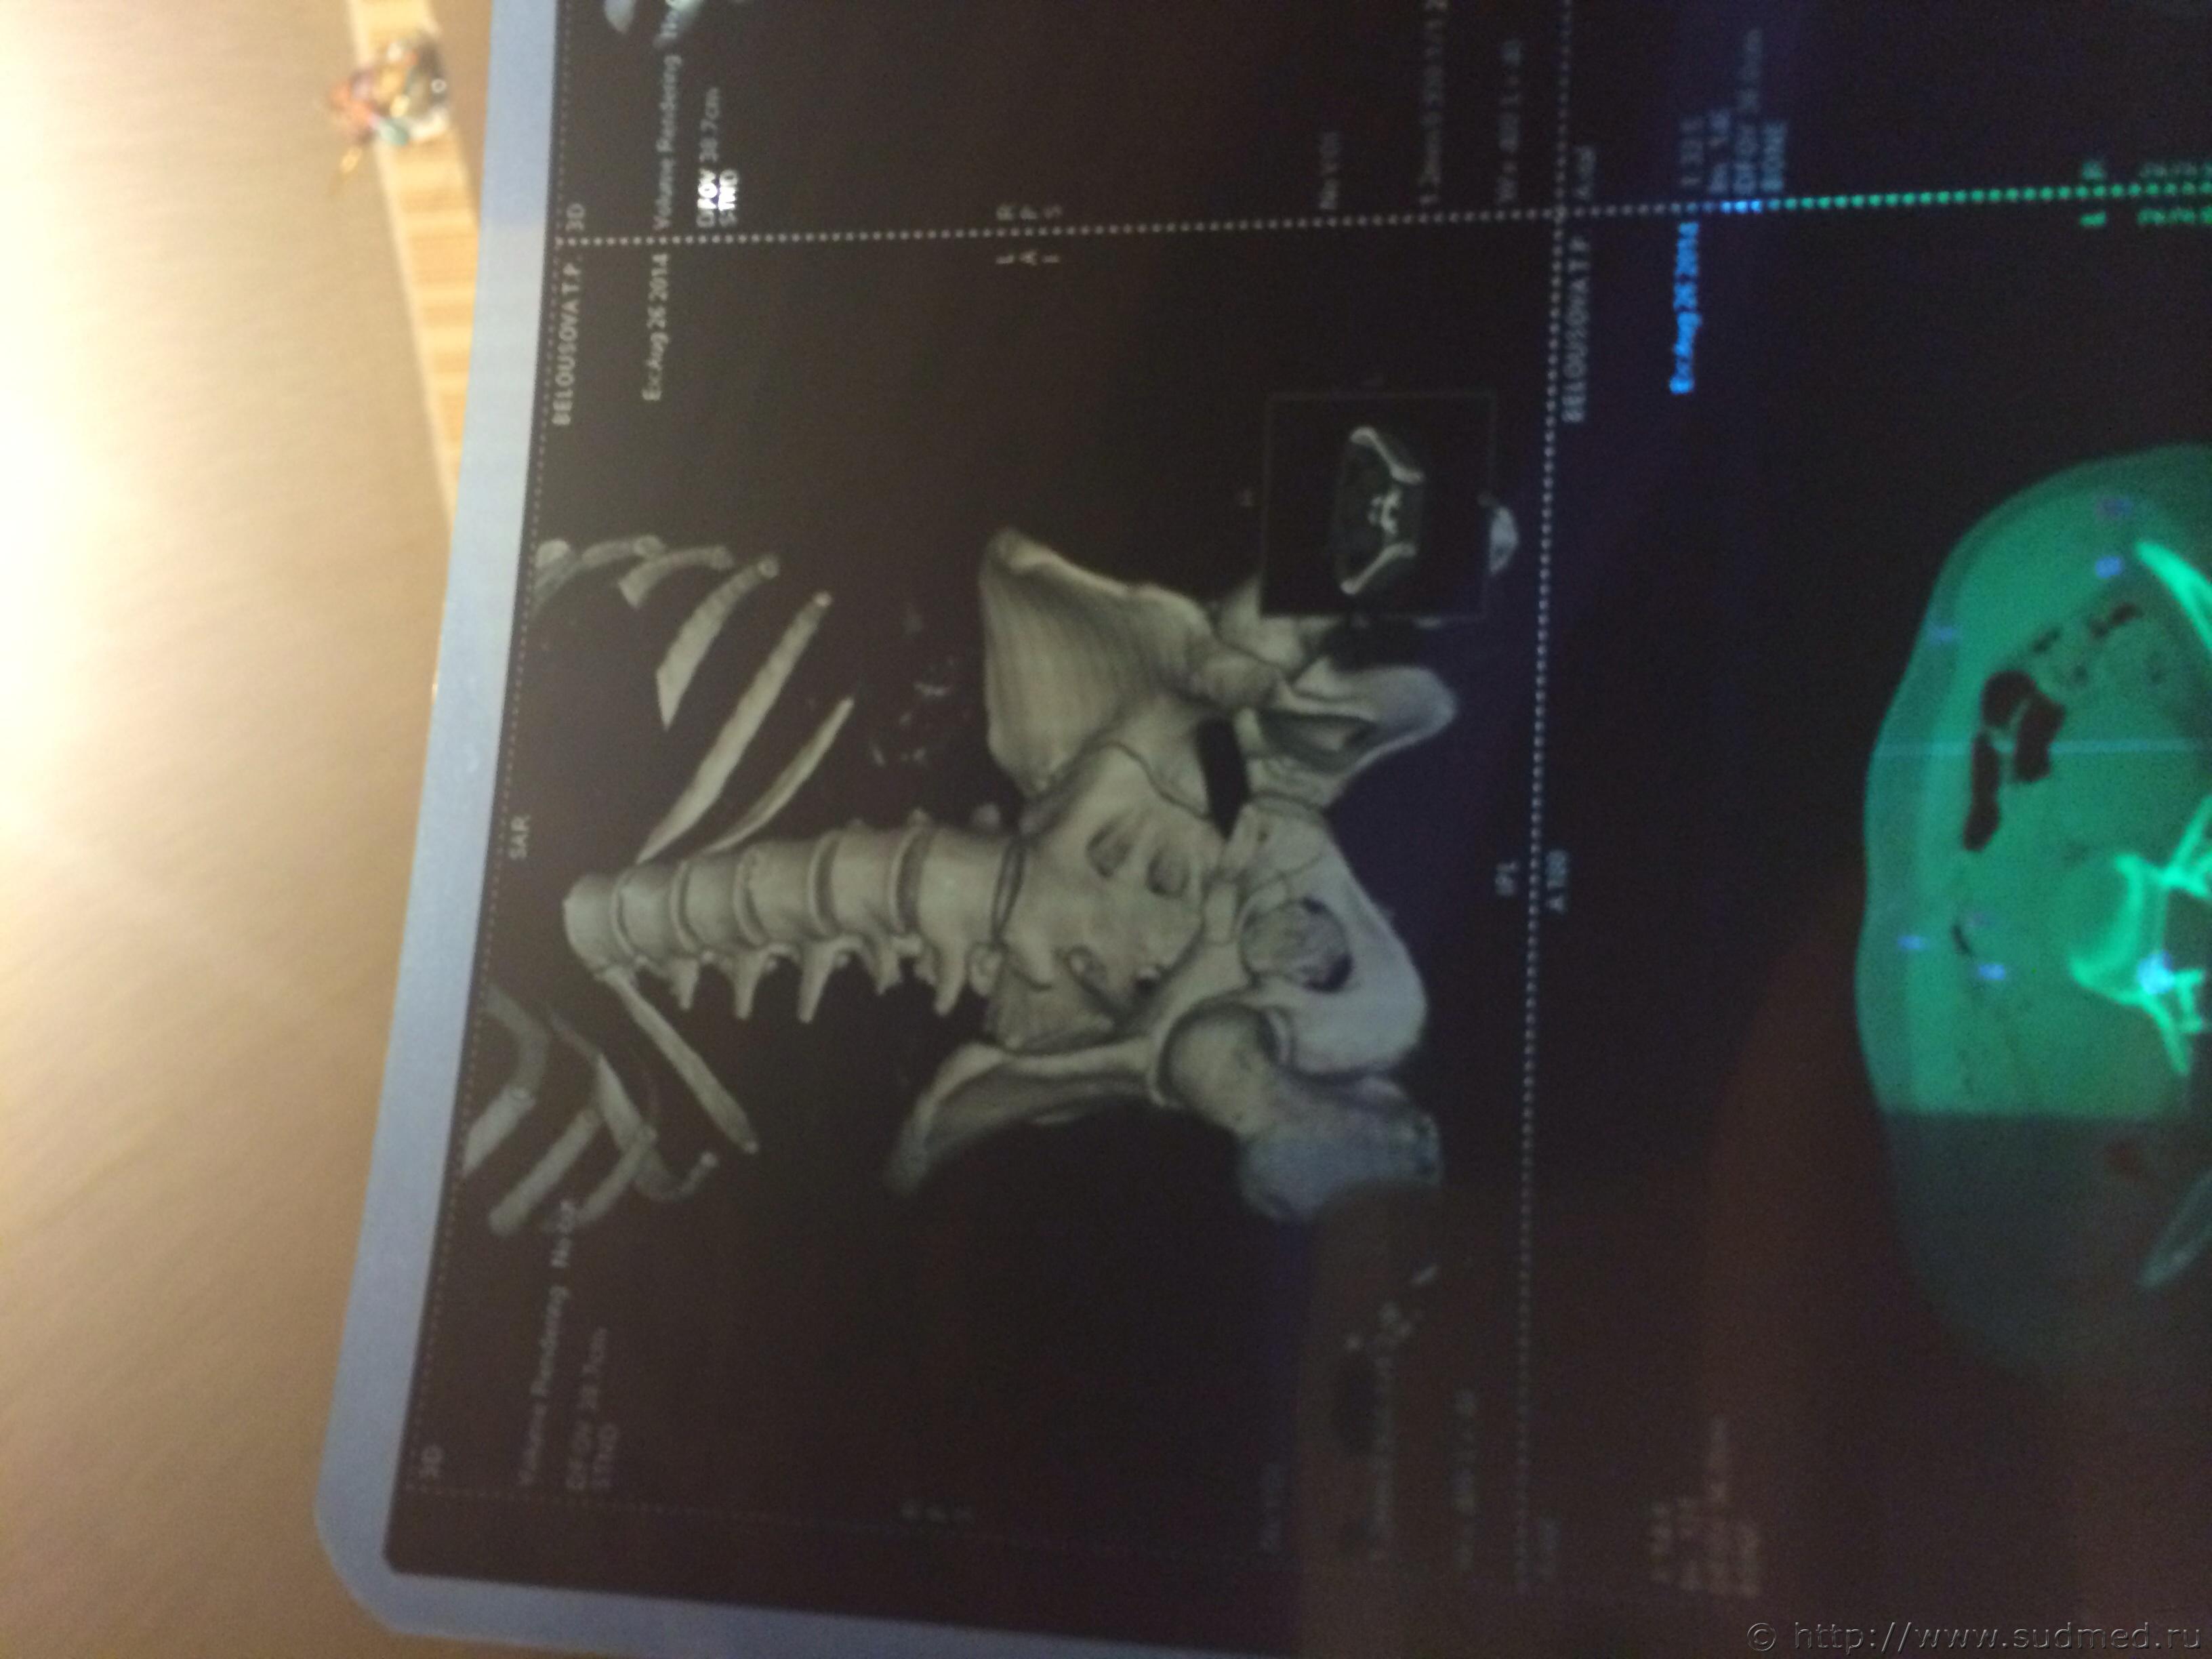

Спасибо! У меня результаты КТ, ошиблась)

КТ

Как мне видится - вертикальный перелом крестца. Тяжкий вред.

Впрочем, оставляю небольшую вероятность, что я не видел все сканы, да и качество их здесь, разумеется, хуже, чем изображение на пленке или на экране компьютера у врача, работающего на томографе.